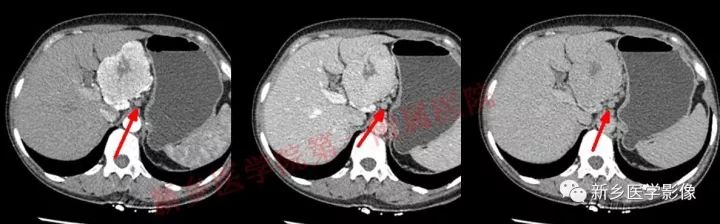

肝胃间胰腺前上方见类圆形肿块,边界较清,大小约8.2cm×4.6cm×5.9cm,密度欠均匀,内见点状钙化,增强呈不均匀明显强化,内见片状低密度灶无强化区,其下部与相邻胰腺分界不清,周围见粗大回流血管影回流至门静脉,病变左侧及腹膜后、胃壁小弯侧见数个卵圆形稍大淋巴结及结节影,部分呈环形强化。

GLNH高强化机制为透明血管型病灶内丰富的毛细血管增生和周边较多粗大的滋养动脉所致。